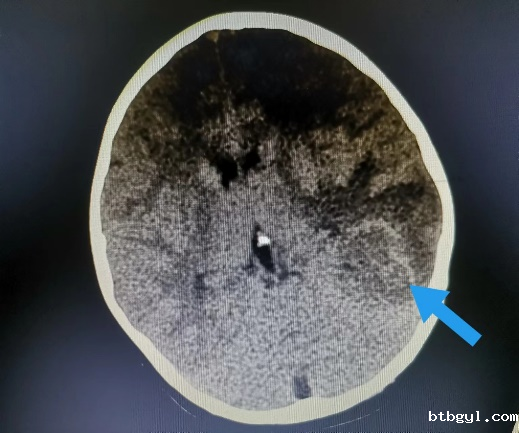

近日,一向身体健康的8岁的小男孩小阳(化名),几天前突然开始剧烈头痛,反复恶心、呕吐,奶奶赶紧把他送到我院就诊。 起初,大家认为小阳只是简单的感冒或则肠胃问题,普通检查没有找到病因,最终在颅脑CT提示下发现小阳“左侧枕叶脑出血伴血肿形成”。 患儿入院影像(左图为颅内出血、右图为胸腔积液及心包积液) 入住神经外科后,考虑到小阳近期并没有受过外伤,依据既往经验,小阳的脑出血可能是先天性血管畸形,但完善相关脑血管检查后却提示小孩脑血管正常,诊断一时陷入了僵局。 仔细问诊 查找蛛丝马迹 经过不断询问,副主任医师汪棋笙了解到小阳来自山区农村,且平时有喝生水和吃生螃蟹的习惯,汪棋笙似乎找到了诊断的关键。回顾了小阳血常规结果嗜酸性粒细胞较正常增高4倍,结合患儿心肺CT提示心包积液、胸腔积液,存在多器官损害表现,汪棋笙高度怀疑小阳就是肺吸虫感染、脑型肺吸虫病。 多方打探 从成都邀请工作人员上门检测 近年来肺吸虫病感染率非常低,肺吸虫血清抗体检测在周边各大医疗中心均已停止开展此项检查,诊断再次陷入困难。经多方打听,最终联系到可以开展此项检测的机构,为此,科室立即联系,邀请工作人员从成都赶来上门抽血检测。最终确立了肺吸虫感染、脑型肺吸虫病的诊断。 寻遍全省 获得特效药 尽管小阳的诊断已明确,可新的问题又再次出现,治疗肺吸虫的特效药物“吡喹酮片”医院及市场上已经无法购得。科室可谓是全员出动,寻遍各级医疗机构,最终从四川省疾控中心获得该药物,治愈了小阳。 患儿出院影像(颅内出血、胸腔积液及心包积液已基本吸收) 特别提醒: 饮用生水或吃了未经煮熟的青蛙、蛇等肉类,容易导致寄生虫感染,寄生虫可进入血管,并通过血液循环进入大脑内生存,引发相关脑病。 肺吸虫是什么? 肺吸虫又称并殖吸虫,是甲壳类哺乳动物的常见人兽共患寄生虫。当它们在组织中迁移时会引发嗜酸性反应,因此我们可以在化验单上看到嗜酸性粒细胞增多。肺吸虫感染人体后主要寄生于肺部,还可异位至脑部、腹部及皮下等部位,引起相应的器官组织病变。 哪些习惯容易招虫? 近年来发病率有所下降,但在部分人或因饮生水、生食或者半生食虾蟹的习惯,导致该病时有发生。 如何预防肺吸虫感染? 1.不要随意喝生水,尤其是河水、小溪水等。 2.切勿吃生的淡水螃蟹、小龙虾等,一定要煮熟。 3.避免食用未煮熟的其它淡水甲壳类动物或来自污染水源的淡水鱼类。 神经外科联系电话:0830-5216264